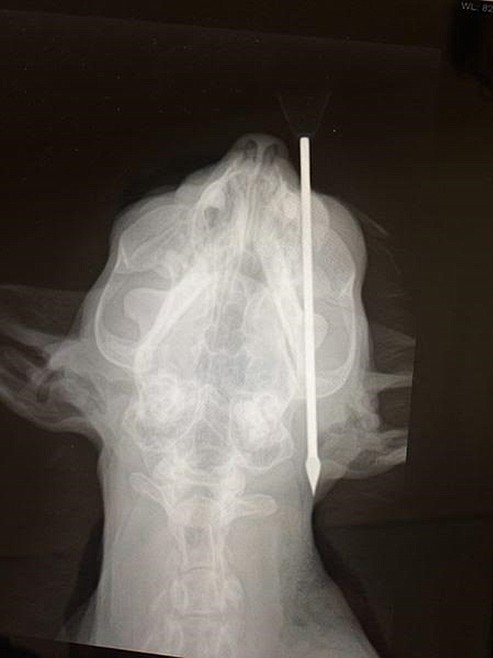

Courtesy image This x-ray image shows how a 4.5-inch blow dart went into Red's head.

COEUR d'ALENE — Finding the suspect who struck Red the cat in the face with a 4.5-inch blow dart just became more lucrative.

Red, an 11-year-old tabby short-hair mix owned by Carson Kelley and his girlfriend, Katelyn Halpin, was shot near an eye on May 12 near Bryan Elementary in Coeur d'Alene. The cat amazingly survived as the dart just missed its brain.

"This cat narrowly escaped with his life after suffering the agony of having a thick, 4-inch dart shot into his head," said PETA Senior Vice President Lisa Lange. "PETA is urging anyone with information about his attacker to come forward immediately, before this culprit hurts anyone else."

Halpin said it is believed Red was shot between 2 and 5 p.m. A roommate of hers discovered the cone end of the blow dart coming out of its head next to its eye.